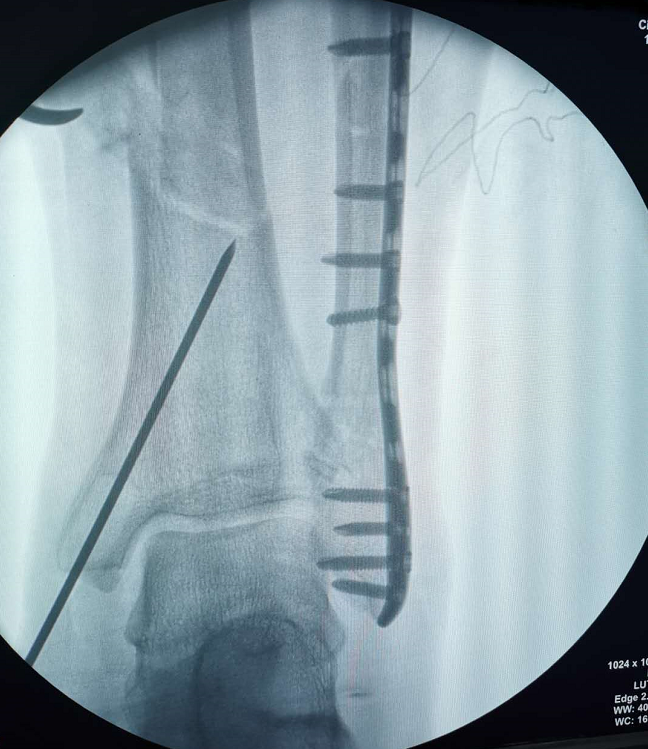

近期,我院骨科四病区刘京升主任团队完成了一例胫腓骨远端骨折合并足部多发骨折患者的治疗,其中应用的胫骨逆行髓内钉技术属全省首例,手术由刘京升主任医师、王凯副主任医师和冯凯医师共同完成。

小腿远端腓骨骨折治疗多采用切开复位钢板内固定,胫骨骨折可选用MIPPO技术钢板固定、胫骨顺行髓内钉及胫骨逆行髓内钉技术,其中MIPPO技术因患者软组织条件差术前消肿时间过长,顺行髓内钉因骨折线位置较低髓内钉远端把持力不足,同时会一定程度影响膝关节活动。而胫骨逆行髓内钉技术作为国内逐渐发展起来的新技术,在处理胫骨远端骨折时具有软组织损伤小、复位及固定简易等优势,十分适合本症状患者。

近年来,四肢骨折微创手术已在我国多地开展,对于符合适应症的患者其创伤小、并发症少、疗效较确切,该技术的首次应用也标志着我院骨科在创伤骨科诊疗技术方面又迈入了新的台阶。